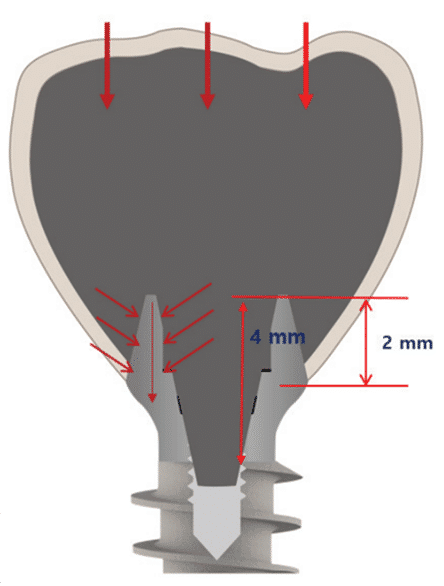

Le Magic Post est conçu avec des connexions externes et internes, offrant un espace de 2 mm pour obtenir l’effet de ferrule à l’extérieur et un espace de 4 mm pour obtenir une connexion interne solide.

Cela permet d’obtenir une double connexion robuste, prévenant le détachement vertical et rotatif de la prothèse. De plus, elle contribue à disperser les forces lors de l’application des forces occlusales, réduisant ainsi considérablement le risque de fracture de l’implant (figure 15).

(Figure 15) Schéma de l’assemblage du Magic Post.